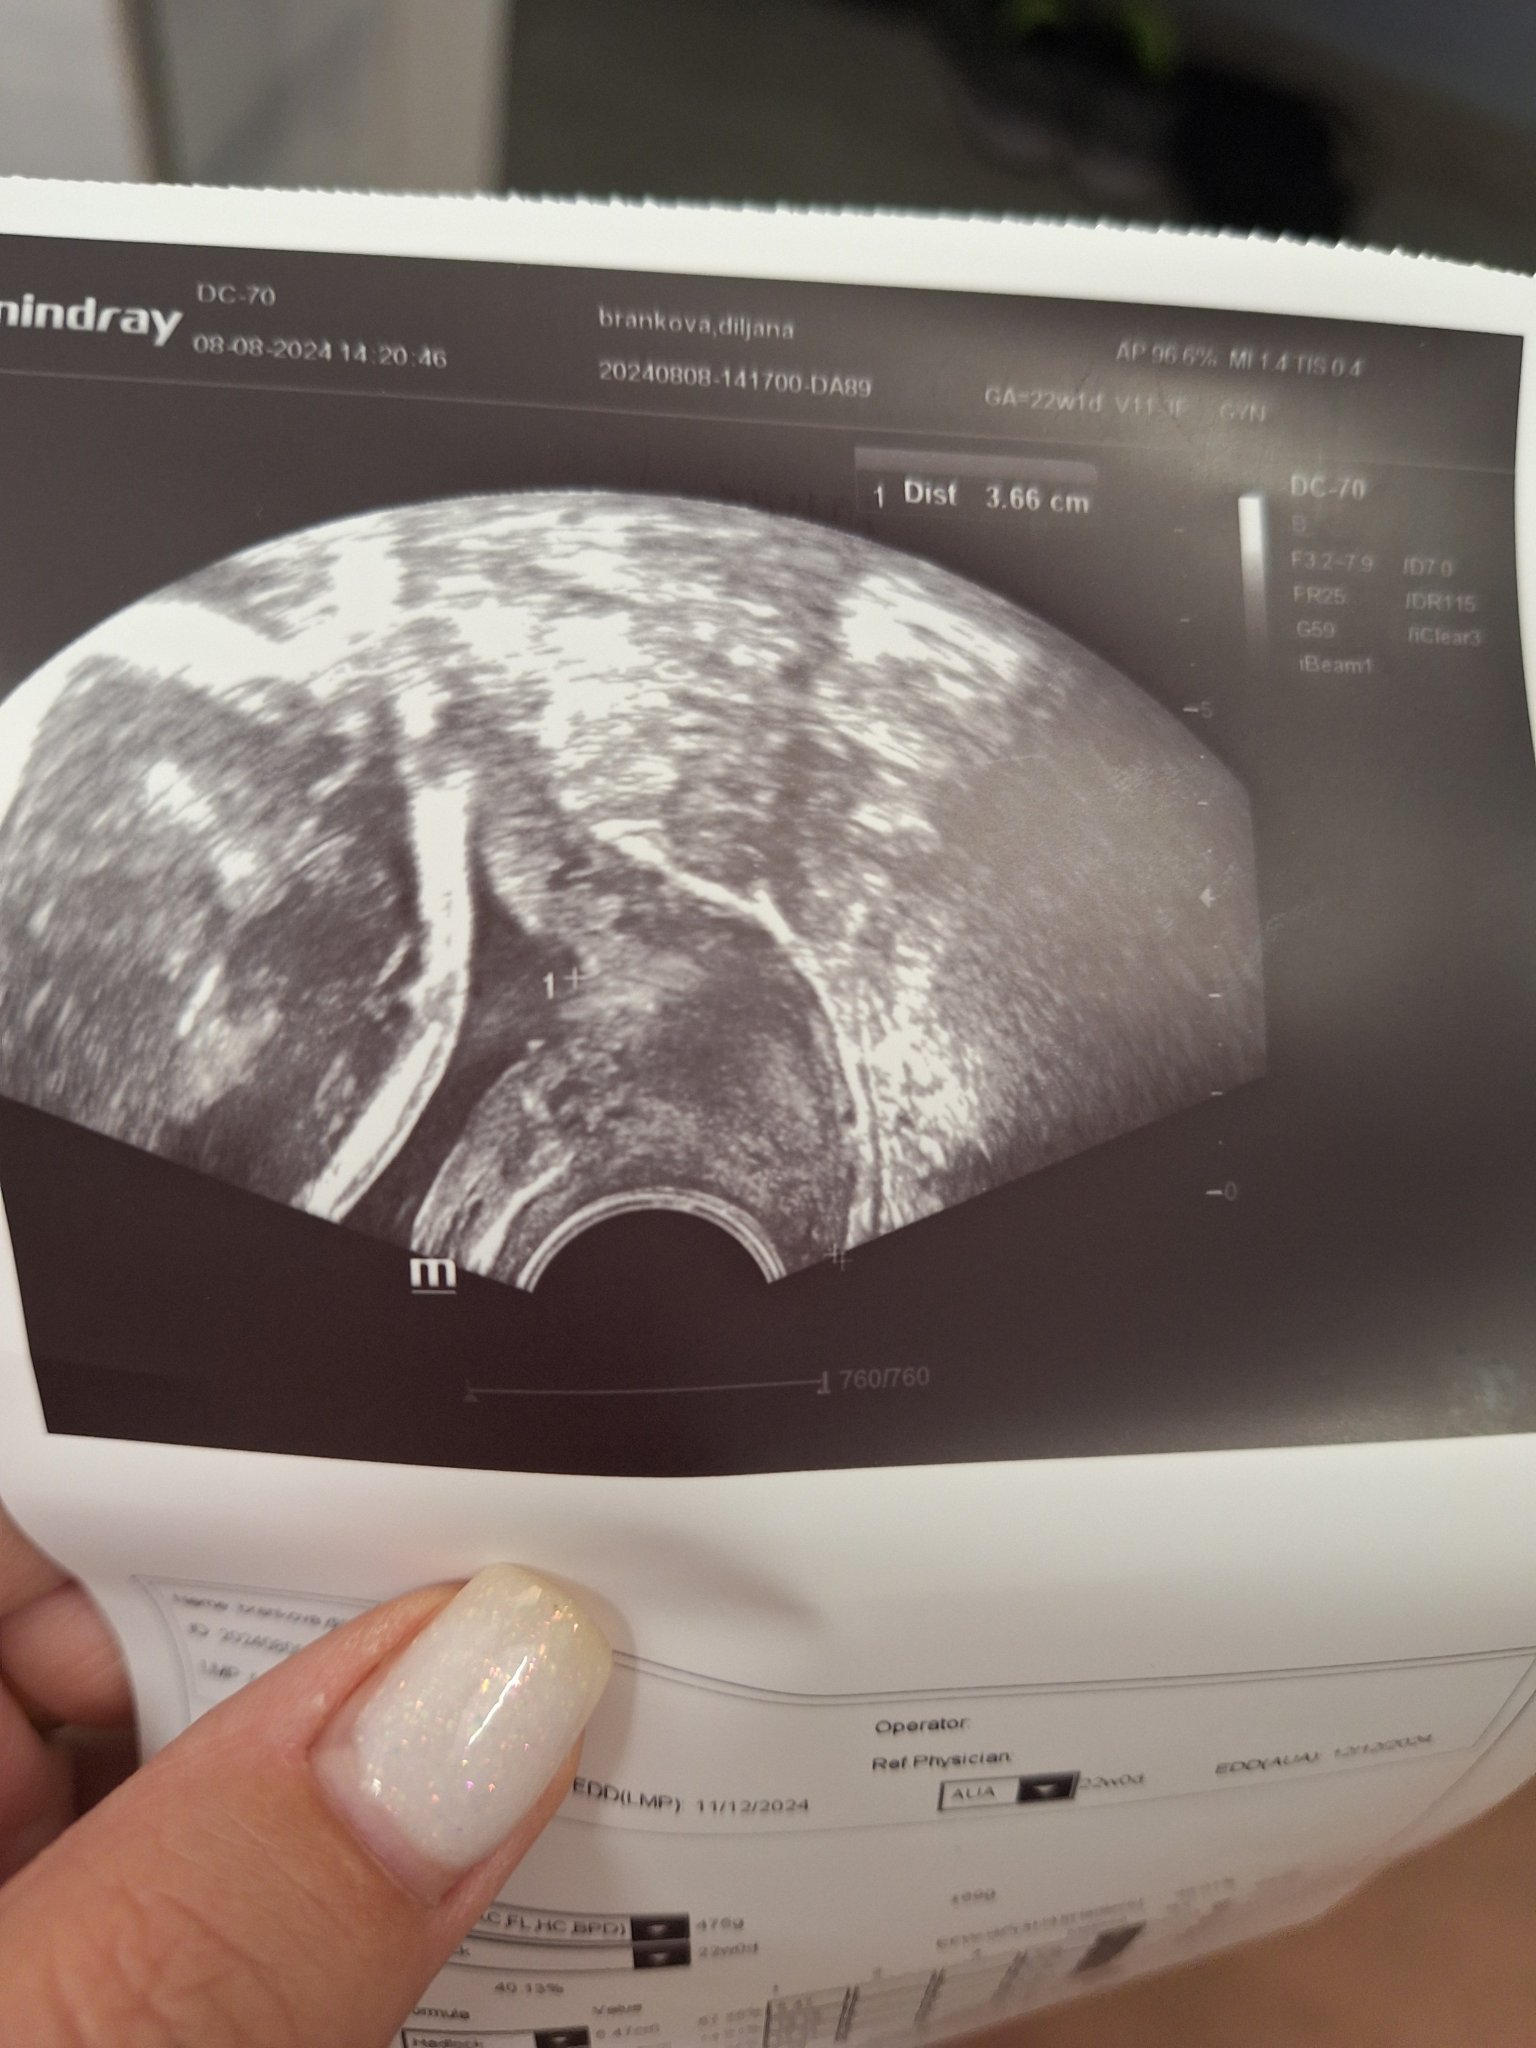

Как участниците обменят информация за здравословното си състояние и прегледите?